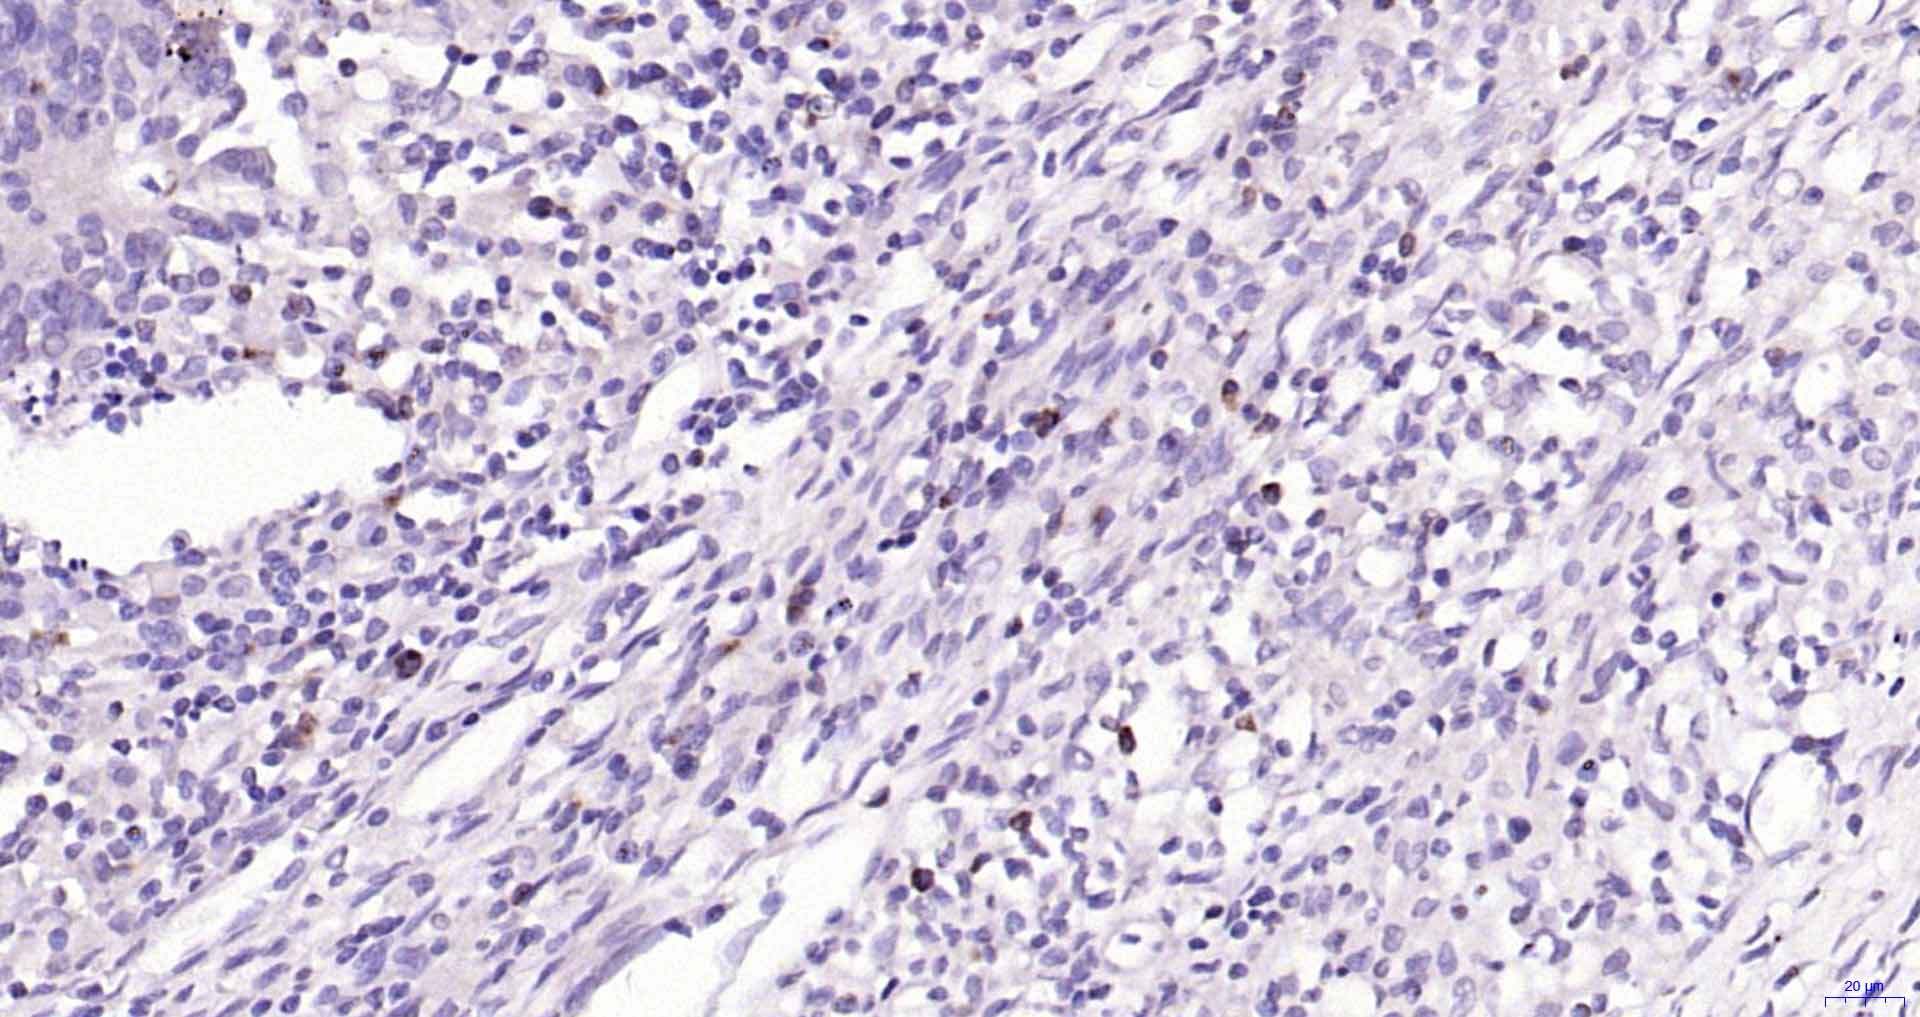

• IHC-P

• IF(IHC-P)

IHC-P IHC-P1:50-200

IF(IHC-P) IFIHC-P1:50-200